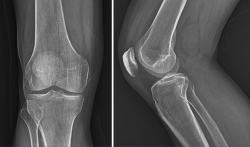

La radiología es útil para el diagnóstico de las fracturas, luxaciones, osteoartritis o para cuantificar las desviaciones axiales y planificar las cirugías de realineación(1).

Es el procedimiento de imagen empleado generalmente como primera elección y es muy útil para la visualización de los elementos óseos, con la limitación que supone la superposición en un mismo plano de todas las estructuras atravesadas por los rayos X.

Deben hacerse proyecciones anteroposterior (AP) y lateral, generalmente con flexión de 30°, y axial de la rótula cuando se sospeche patología de esta; y proyecciones especiales oblicuas o laterales, proyecciones forzadas de varo o valgo, y AP en 45°, para valorar mejor la interlínea articular(2).

La gonartrosis es la causa más frecuente del dolor de rodilla después de los 50 años. En la radiografía se observa una reducción de la interlínea femorotibial o femoropatelar, y una osteofitosis marginal (Figura 6).